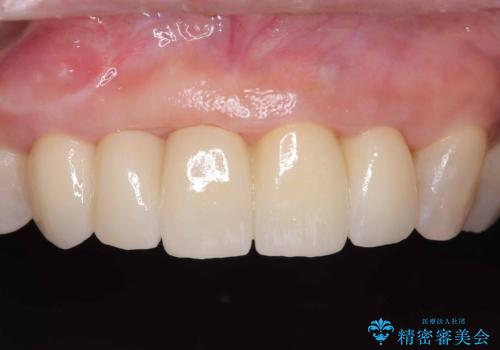

今回のケースでも、しっかりと固定が得られたため、手術は1回で終了し、短期間でオールセラミッククラウンまで装着することができました。患者様も術後の痛みはなく、処方した痛み止めも服用されなかったとのことです。

これだけ大きな病変があったにもかかわらず、痛みがなく短期間で治療が終わったことに加え、被せ物の色も周囲の歯に調和し美しく仕上がったことに、大変ご満足いただけました。